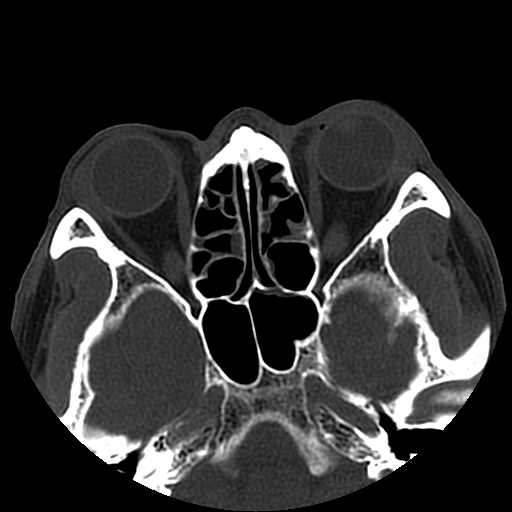

以下是引用liaoqiang在2008-7-16 21:15:00的发言:[br]右侧鼻骨骨折

以下是引用zxd95在2008-7-16 21:39:00的发言:[br]右侧上颌骨额突骨折。[br][br][br][br]